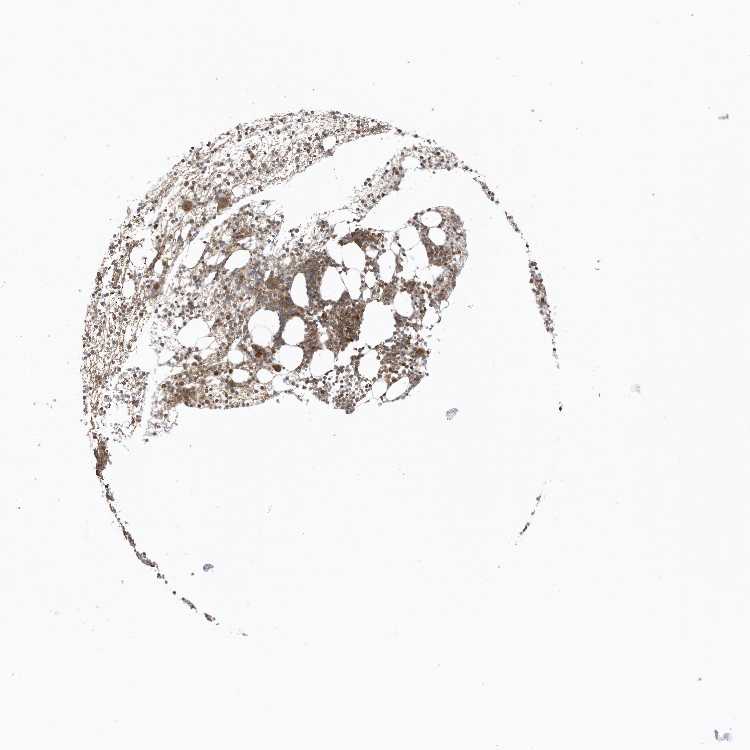

BONE MARROW - Antibody stainingi

Antibody staining in the annotated cell types in the current human tissue is reported as not detected, low, medium, or high, based on conventional immunohistochemistry profiling in selected tissues. This score is based on the combination of the staining intensity and fraction of stained cells.

Each image is clickable and will lead to virtual microscopy that enables deeper exploration of all samples and also displays staining intensity scores, fraction scores and subcellular localization as well as patient and tissue information for each sample.

Antibody HPA035399

Hematopoietic cells Medium